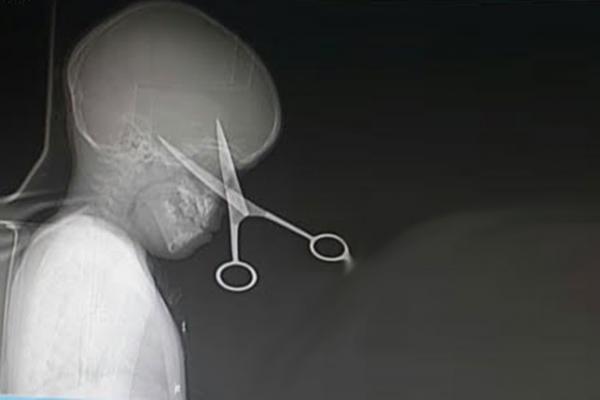

والد يؤدب ابنته بمقص إخترق رأسها - صور

في قصة غريبة، أصيبت طفلة تبلغ من العمر 10 سنوات باختراق طرف من مقص حاد في الجمجمة بعد أن ألقاه والدها نحوها في محاولة منه لتأديبها.

نقلت صحيفة "ديلي ميل" البريطانية الحادث الذي وقع في مدينة شنغهاي عندما ألقى الأب المقص نحو إبنته ليستقر بجمجمتها عن طريق الخطأ، أثناء محاولته تخويفها بينما تلعب أثناء أداء واجباتها المدرسية.

وأكدت أن هذا الحادث مر كالصاعقة على الاب، الذي سارع الى طلب سيارة الاسعاف التي نقلت الطفلة بشكل سريع إلى المستشفى لإزالة المقص البالغ طوله 6 بوصات من رأسها.

وأكد الأطباء بعد معاينة الطفلة وإجراء الصور والفحوصات اللازمة أنه لحسن الحظ لم يخترق الأوعية الدموية الرئيسية بالرأس.